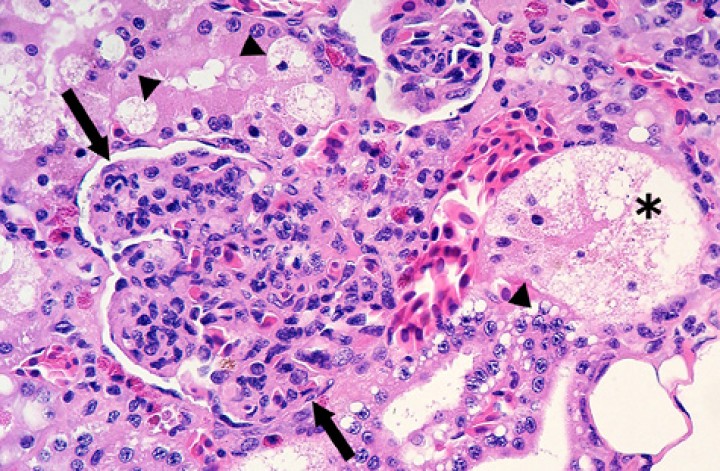

En cuanto a las glomerulonefritis, eran predominantemente membranoproliferativas o mesangioproliferativas (Fig. 13). De los 10 anfibios afectados, 7 mostraban enfermedades bacterianas sistémicas (6 de los cuales correspondían a micobacteriosis) y 7 nematodiasis concurrentes.

<p>Riñón; sapito balear (<em>Alytes muletensis</em>). Se observa hipercelularidad intensa con engrosamiento leve del mesangio de un glomérulo (flechas) e infiltración y marginación de células inflamatorias en capilares (glomerulonefritis mesangioproliferativa); arriba en el centro se distingue un glomérulo no afectado para comparación. Una lesión adicional consiste en vacuolización citoplasmática del epitelio tubular o degeneración vacuolar franca (cabezas de flecha) y necrosis (asterisco). Hematoxilina-eosina, x480.</p>

Riñón; sapito balear (Alytes muletensis). Se observa hipercelularidad intensa con engrosamiento leve del mesangio de un glomérulo (flechas) e infiltración y marginación de células inflamatorias en capilares (glomerulonefritis mesangioproliferativa); arriba en el centro se distingue un glomérulo no afectado para comparación. Una lesión adicional consiste en vacuolización citoplasmática del epitelio tubular o degeneración vacuolar franca (cabezas de flecha) y necrosis (asterisco). Hematoxilina-eosina, x480.